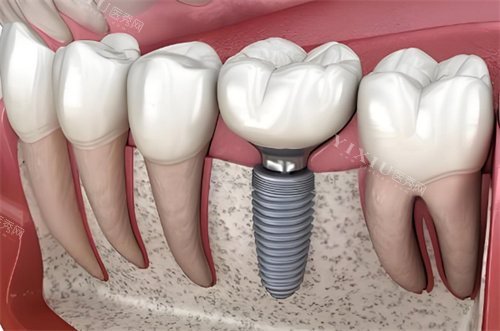

在牙齿缺失的困扰下,种植牙无疑成为了众多患者重获健康与自信笑容的希望之光。而美国杰美 zimmer 种植体,作为种植牙领域的高人气品牌,备受关注。它是否真的靠谱?下面我们就从多个方面来深入了解一下。

独特的根方开孔设计允许骨头直接生长到种植体内部,大大增强了种植体与骨骼的结合度。螺纹设计有助于增加骨密度,提高种植体的稳定性。特有的减压孔设计能减轻种植体植入后的骨膨胀不适感,提高患者的舒适度,并有助于骨的保存。